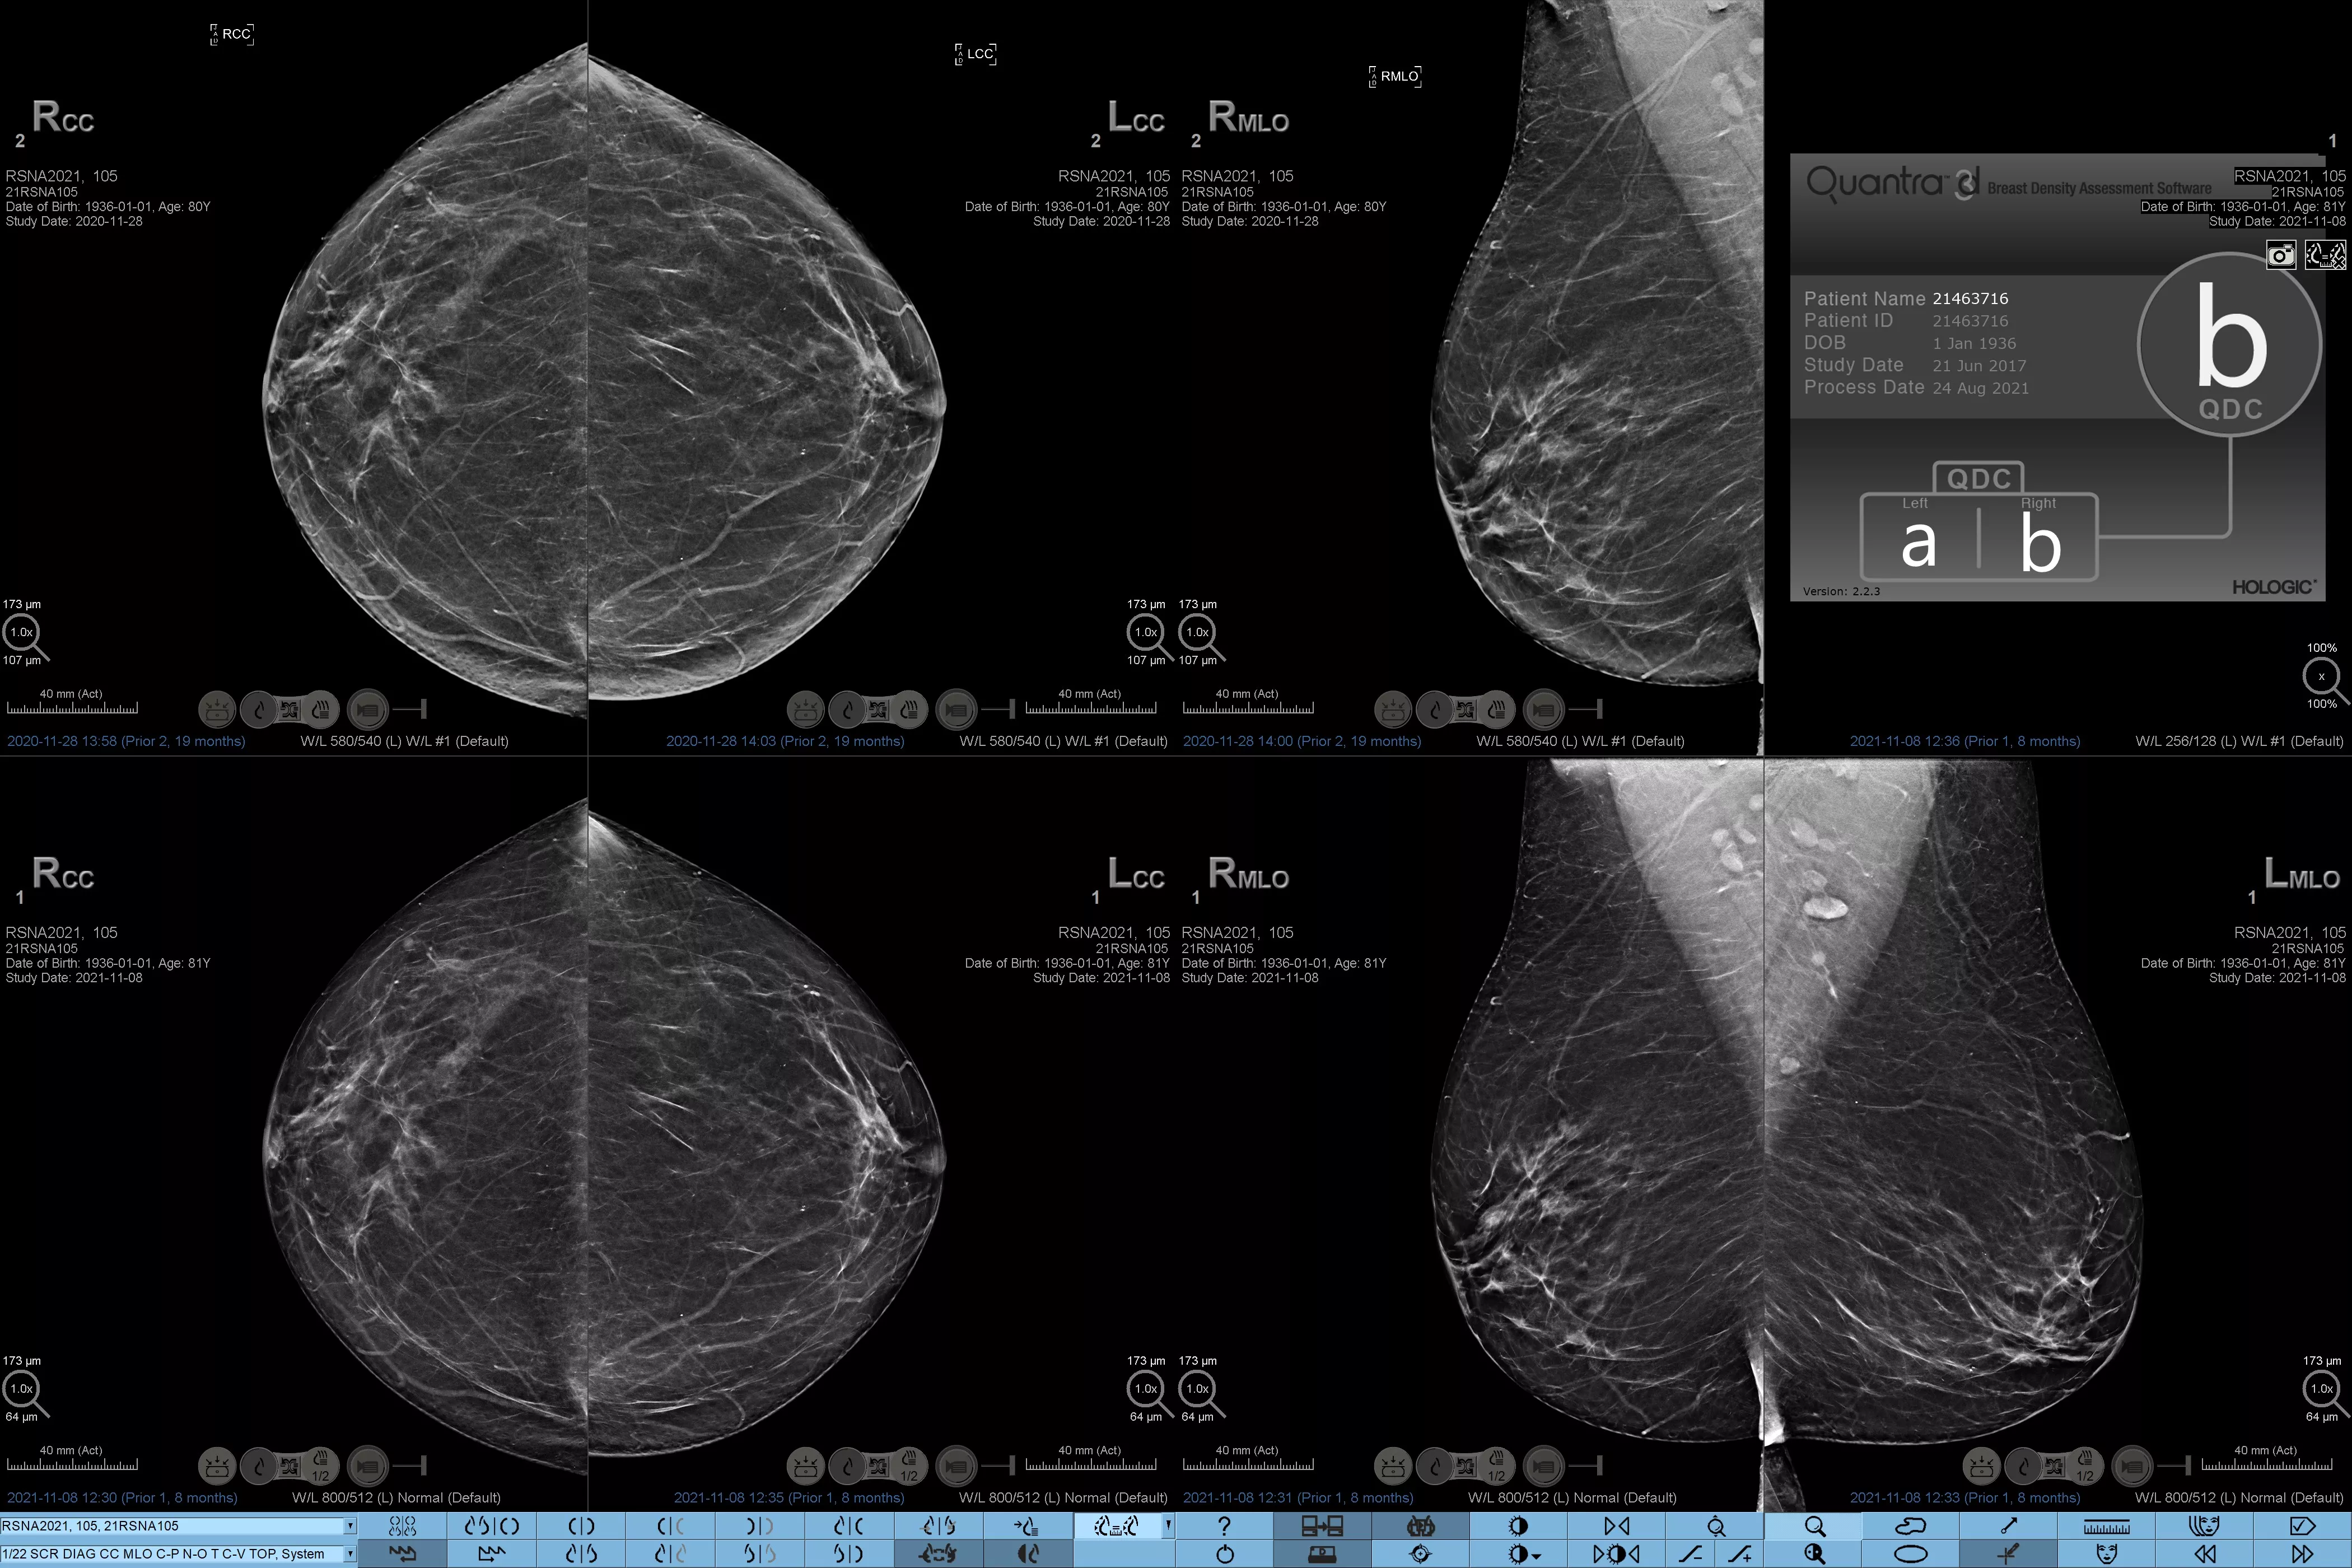

È noto che una maggiore densità del tessuto aumenta il rischio di tumore della mammella.1 È pertanto essenziale effettuare un'analisi accurata e obiettiva. Grazie alle funzionalità di machine learning, il software della tecnologia Quantra analizza le immagini 2D™ e di tomosintesi per evidenziare la distribuzione e l'aspetto del tessuto parenchimale. Classifica le mammelle in quattro categorie in base alla composizione, in linea con le indicazioni del BI-RADS Atlas dell'American College of Radiology (ACR), 5a edizione.2

*I punteggi si basano sulle categorie ACR BI-RADS, in conformità con le linee guida riviste del BI-RADS Atlas dell'American College of Radiation (ACR), 5a edizione. Per determinare la densità si tiene conto della struttura e dell'aspetto del tessuto rispetto al volume.

8. Categorie di densità del tessuto mammario descritte in ACR BI-RADS Atlas.